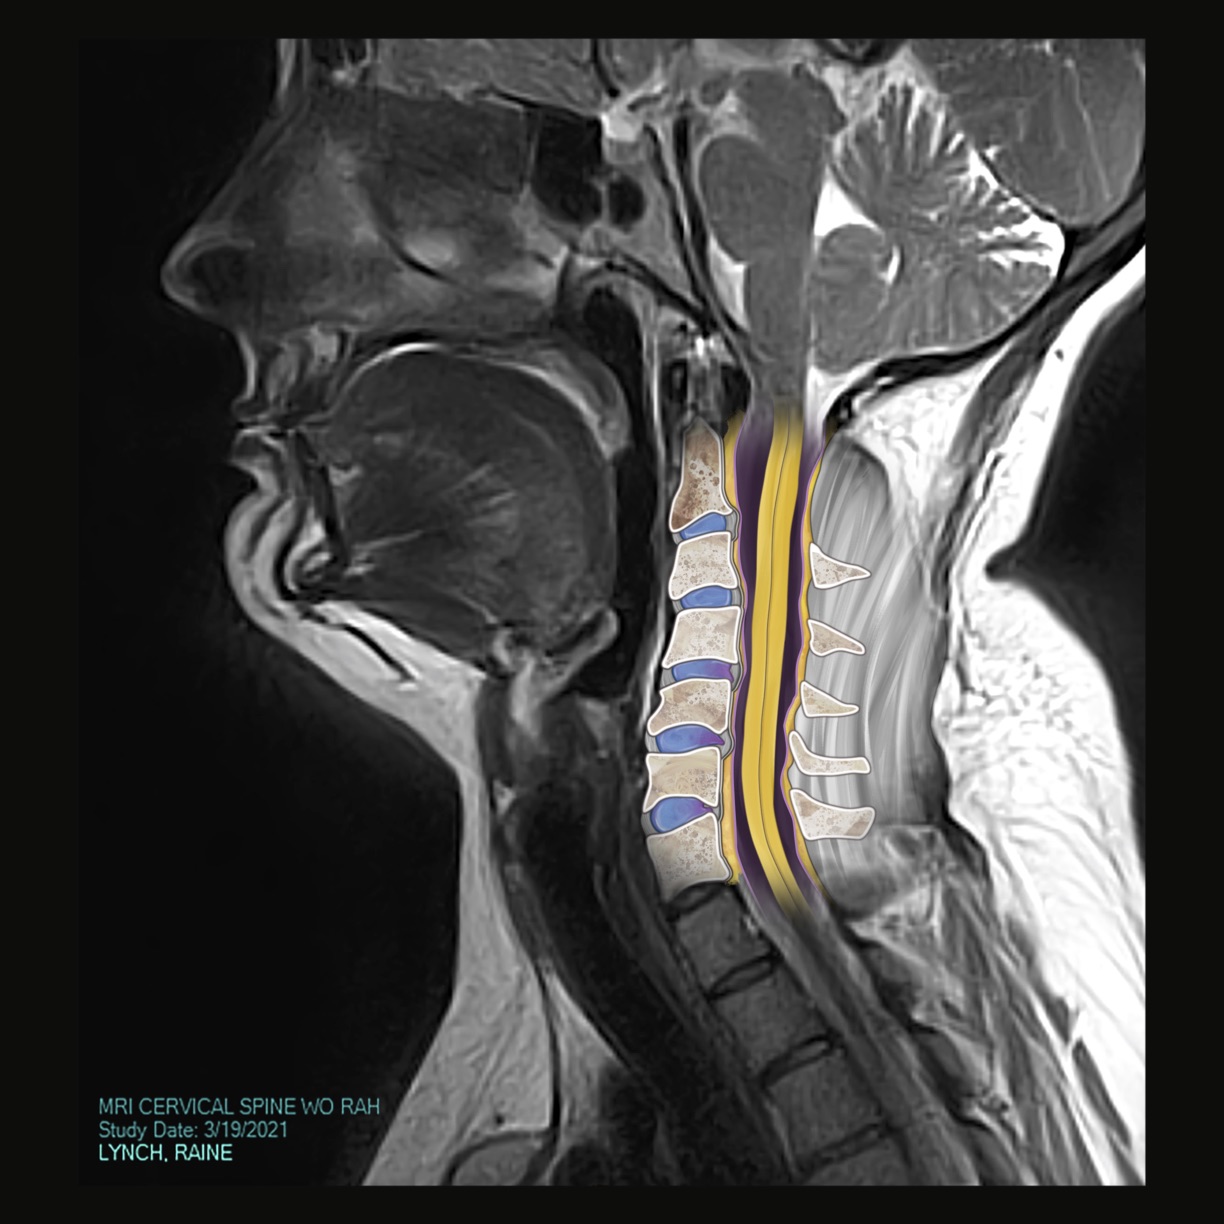

CT scans, MRIs, and X-Rays are all, in a way, portraits of the patient. Films that result from a diagnostic exam display information that is deeply intimate by nature but is often incomprehensible to the patient. The patient learns about themselves and their condition, whether chronic or newly diagnosed, from the words of their physician. Someone without any medical training sees themself as a series of black, white, and gray shapes on a computer screen or printed out on a film. Flesh and bone are abstracted in a way that disconnects them from the body which they represent.

This abstraction and disconnection creates a complicated encounter – how does one relate to an image of themselves when, from their perspective, it looks like little more than television static?

In instances like this where an artist is given a prompt, platform, and permission to create, it is possible to unify select individuals with their films. A patient is elevated to an individual human being by linking a face, name, and snippets of their personality with what would otherwise be a diagnostic assessment reserved for the eyes of physicians. This exhibition is about connecting the individual to themselves and others, and furthering the integration of art and science. Disclosure aims to dignify a patient and their condition through a work of art, and bridge the gap between the results of a diagnostic medical exam and what makes us human.